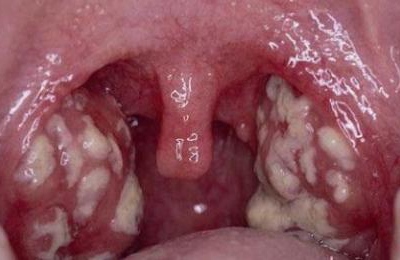

История болезни хронический тонзиллит характеризуется следующими признаками:

- боли в горле;

- гнойные налеты на миндалинах;

- температура обычно нормальная, но в период обострения к вечеру температура у взрослых и детей может быть субфебрильной.